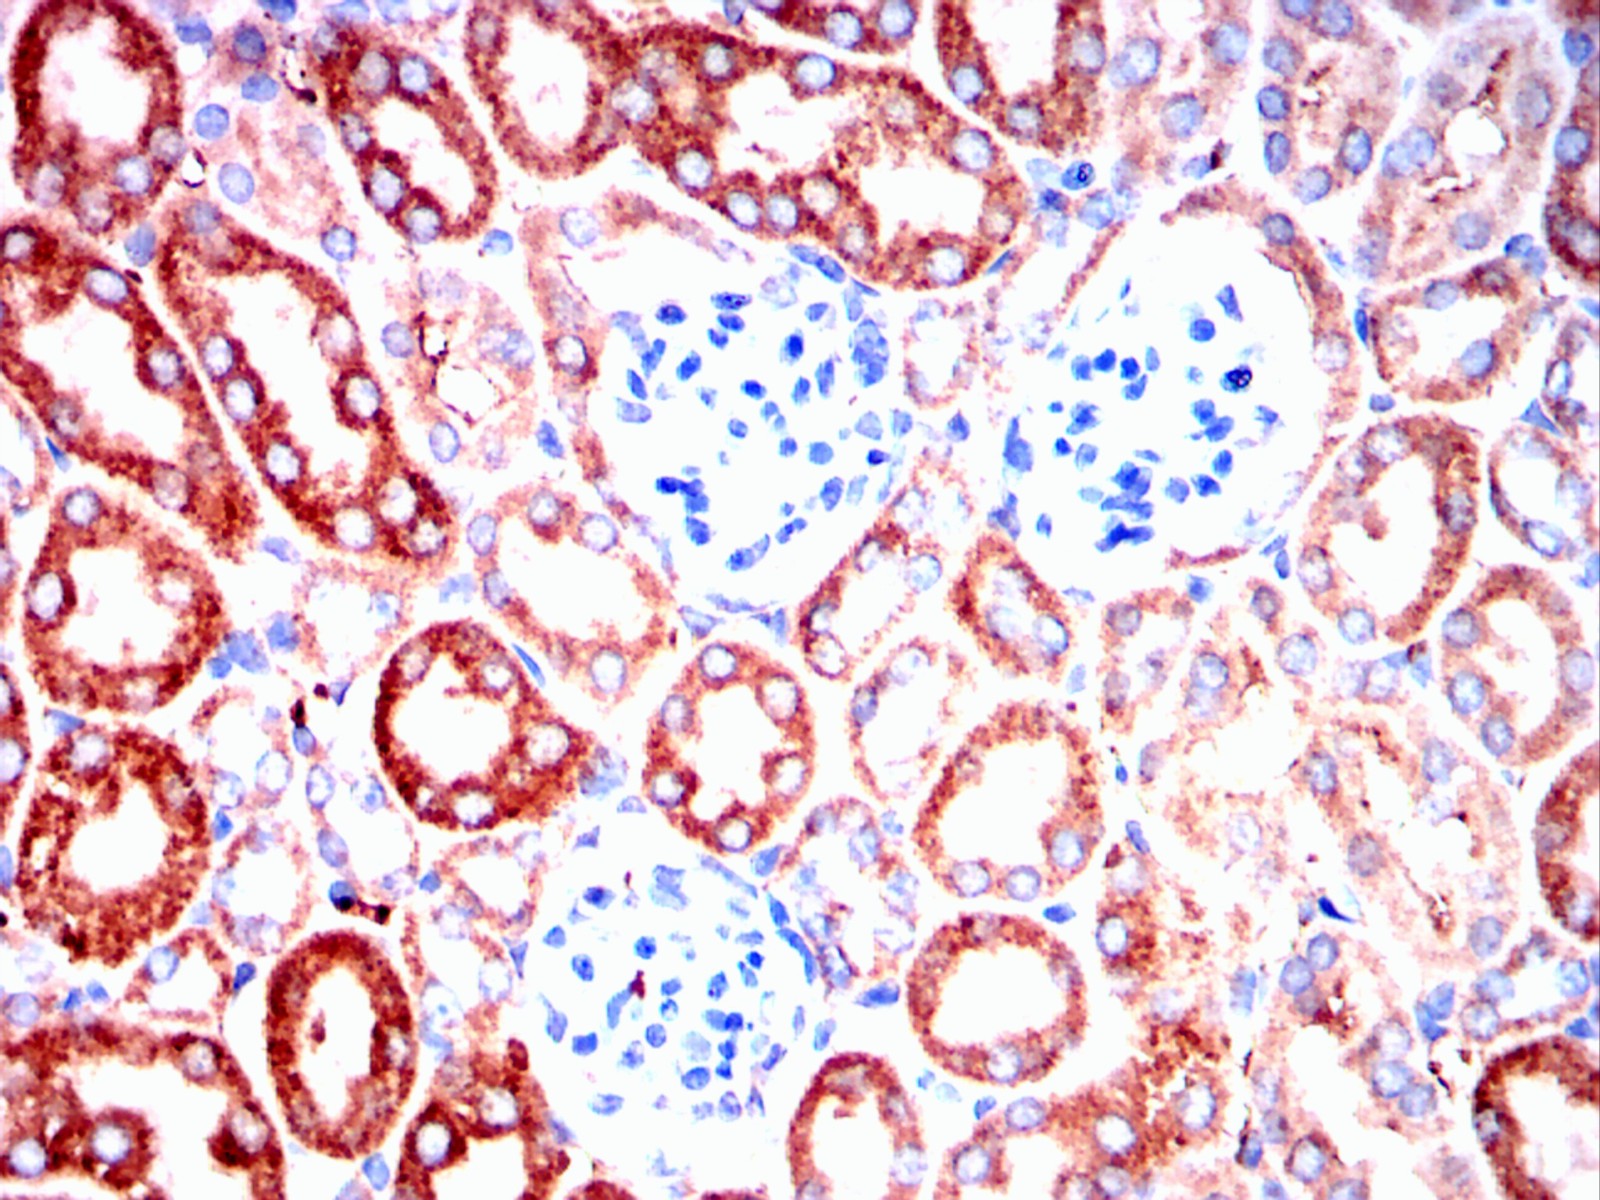

Immunohistochemical analysis of paraffin-embedded mouse kidney tissues using ERBB3 mouse mAb with DAB staining.

Immunohistochemical analysis of paraffin-embedded rat kidney tissues using ERBB3 mouse mAb with DAB staining.

Immunohistochemical analysis of paraffin-embedded rabbit kidney tissues using ERBB3 mouse mAb with DAB staining.